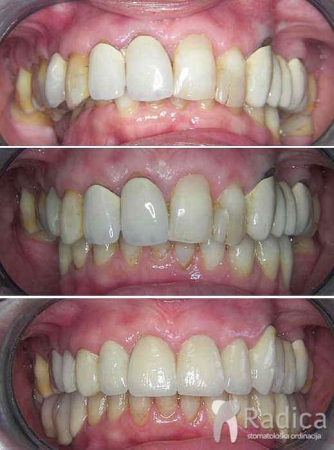

U sljedećem primjeru je fiksna ortodontska terapija rađena samo u donjoj čeljusti. Nakon toga su napravljeni novi protetski radovi u gornjoj i donjoj čeljusti – rad dr. Gorana Radice.

Na sljedećoj slici se mogu vidjeti početak i kraj ortodontske i protetske terapije. Protetske radove radio je dr. Goran Radica.